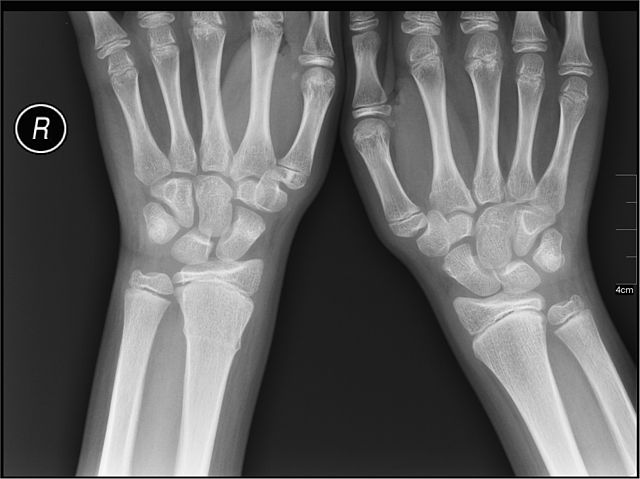

The evaluation of pediatric elbow radiographs in the setting of acute trauma may be challenging for many emergency department physicians, orthopedic surgeons, and radiologists. Pediatric elbow anatomy | radiologypics.com. Diagnostic difficulties stem both from the complex developmental anatomy of the elbow and from significant differences. You can test your knowledge on pediatric elbow fractures with these interactive cases.